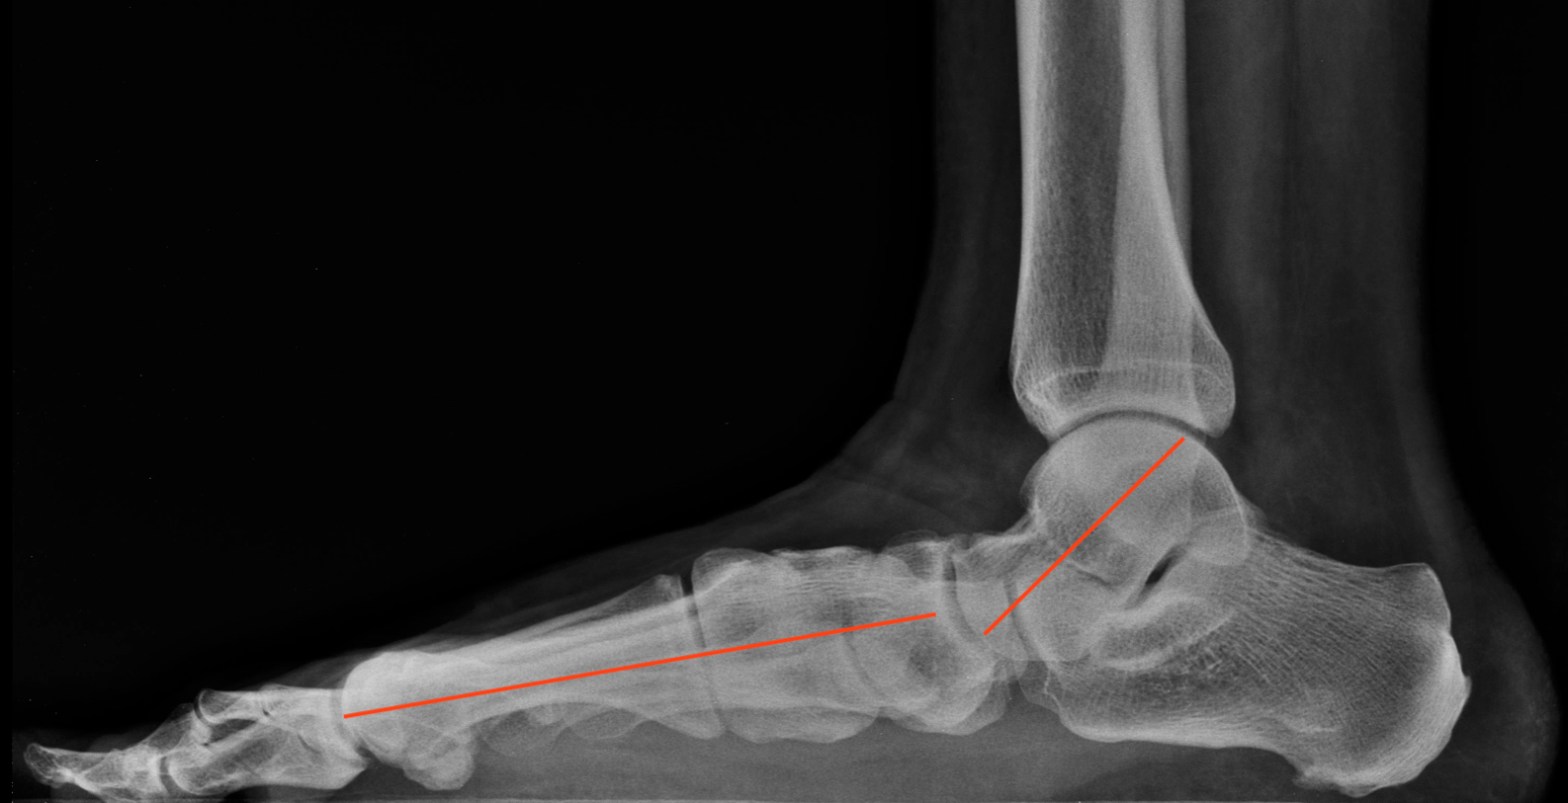

Surgery must correct all components of a deformity that can be quite complex. There are three different lines of motion that are involved in the flat foot deformity. Each individual case has a different arrangement, where some feet are more deformed in one or two lines of motion compared with others. The abnormal motions that dominate the deformity are the ones the surgeon needs to concentrate on, as this will affect their choice of surgical procedure. Different surgical procedures have been developed to deal with the many nuances of the flat foot deformity. A typical flat foot reconstructive surgery involves several different individual procedures to correct each component of the deformity. The flat foot deformity can involve a shifting of the foot outward, a bending of the foot upward, and/or a rolling of the foot inward toward the big toe side. By addressing the components that dominate the deformity, a surgeon can effectively reconstruct the foot to obtain better foot structure. These procedures involve various combinations of bone cuts and soft tissue procedures that rotate, flex downward, or lengthen the foot. More flexible deformities can tolerate the use of a blocking cone-like implant that keeps the foot from flattening, especially in younger patients. Given the nature of the bone cuts, the foot and leg is usually immobilized during the recovery period, which can take two to three months before regular shoes can be worn. Patients with the implant recover much faster.